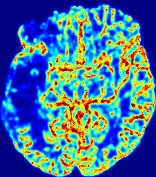

Figure 5: Predicted concentration time series for the same patient shown in Fig. 3, where (i)-(vi) correspond to slices #1-6 respectively. Each grouped row displays (a) the measured concentration image sequences and (b) the predicted concentrations at corresponding time points.

To better illustrate the prediction accuracy, and therefore the estimation accuracy of 𝐕𝐕{\bf V} and D𝐷{D}, of PIANO, we provide the corresponding predicted time-series of CA concentration images in Fig. 5 and Fig. 6 for the same patients in Fig. 3 and Fig. 4, respectively. We see that PIANO is capable of predicting the CA concentration given their initial state, indicating its ability to successfully capture 𝐕𝐕{\bf V} and D𝐷{D}. Note that although the concentration values for these two patients differ considerably, caused by the different total volume of injected CA, PIANO is still able to provide plausible estimates.